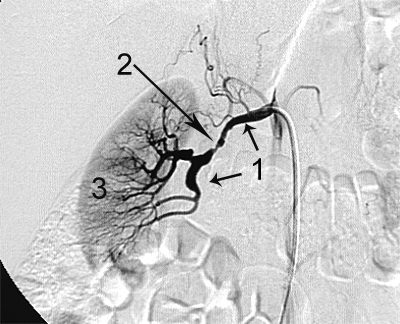

Приклади ангіограм:

стеноз правої ниркової артерії    пухлина підшлункової залози

Ниркова артерія (1), критичне звуження

ниркової артерії, (2) паренхіма нирки (3)

Артерії: загальна печінкова(1),

праві печінкові (2), ліва печінкова (3),

селезінкова (4), пухлина підшлункової залози (5).